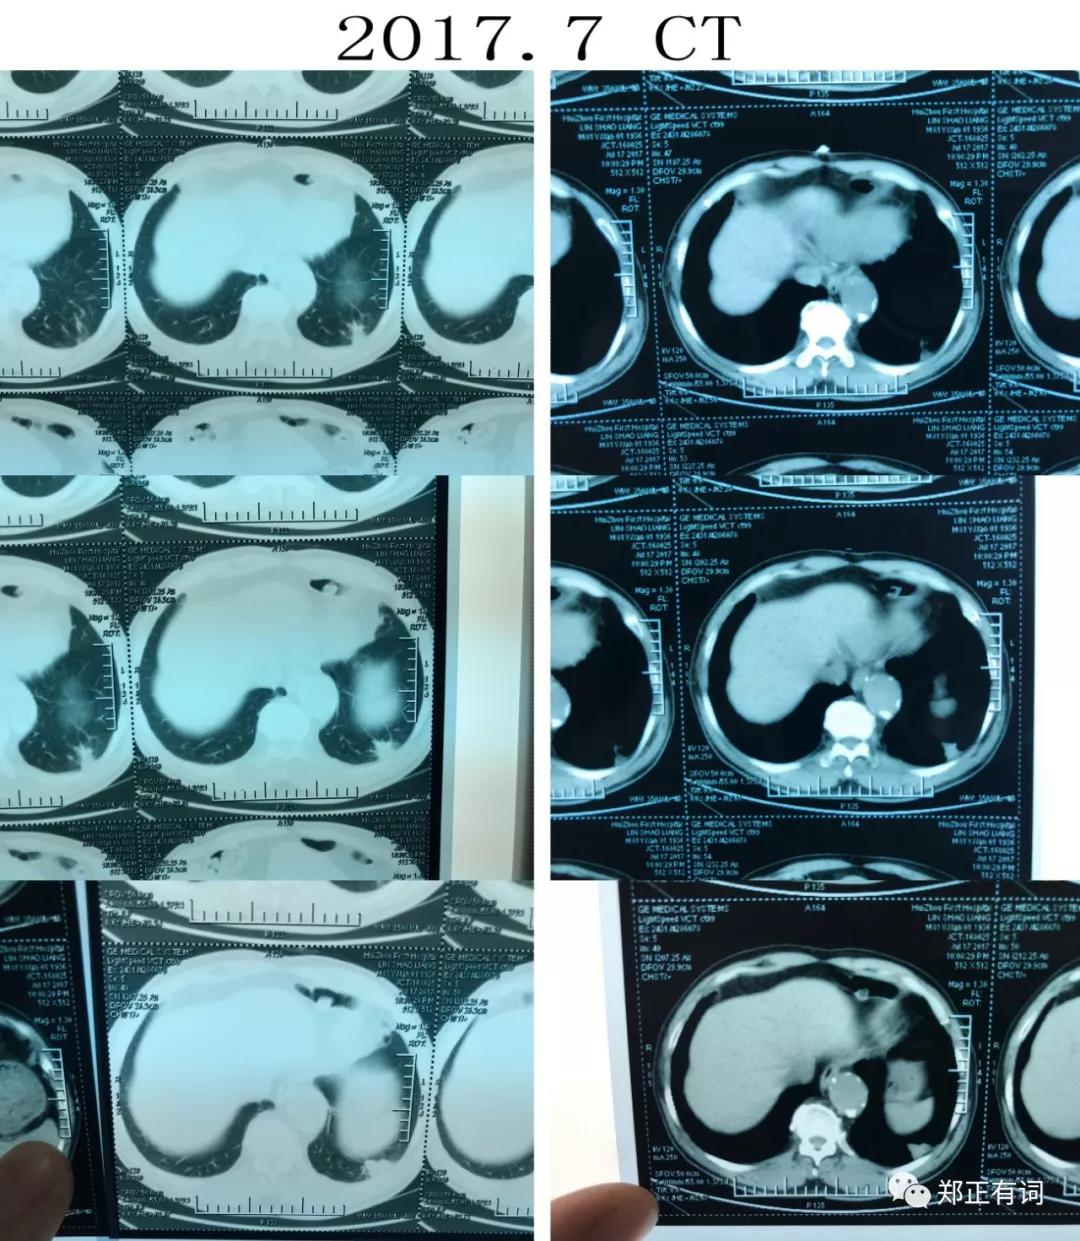

上面是2017.7~2018.11反复随访复查的CT片子。

可见,2017.7就诊时就在右上肺确切的看到异常病灶了,大小为17*15mm。

2018.6复查CT,提示病灶增大,大小为45*34mm。

而到了2018.11复查CT,提示病灶进一步扩大,大小为50*34mm。

于是,从2017.7开始,由着肿瘤生长,从当初最大径不足2cm,到现在最大径5cm。

这是纵隔窗的比较,

从中我们可以看出,早在2017.7,那个异常病灶已经有实性成分了;

在2017.7到2018.6期间,肺部病灶增大,而纵隔淋巴结并无显著差异;

2018.6到2018.11期间,伴随着肺部病灶的增大,出现了多发、多站的纵隔淋巴结肿大。

说明了什么?

说明了除了肿瘤本身在进展,纵隔淋巴结也出现转移了!

2017.7,临床分期 T1bN0M0 IA期

2018.6,临床分期 T2bN0M0 IIA期

2018.11,临床分期 T2bN2M0 IIIA期